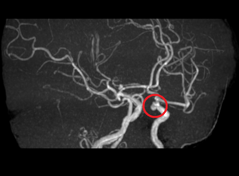

・脳動脈瘤

脳の血管にできるこぶで、破裂するとくも膜下出血の原因となることがあります。

実際の異常所見

![]() 脳動脈瘤 |

無症状でもこのような所見がみられることがあります。このように早期で発見し適切な対策を行うことで、病気の進行を遅らせたり、予防することが可能になります。